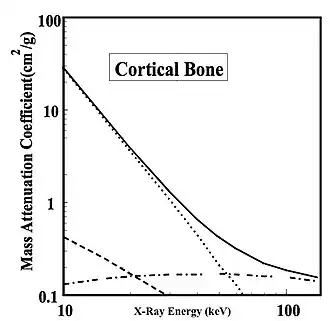

Bone

- In contrast to muscle, the situation for cortical bone is shown in Figure 3.7. Note first that the total attenuation is greater than for muscle, at all except the higher X-ray energies. Secondly, note that attenuation due to the photoelectric effect decreases, once again, almost linearly with energy and becomes less dominant than Compton scatter above about 40 keV. And thirdly, note that attenuation due to the Compton effect is reasonably constant over the energy range at, once again, ~0.2 cm2/g, while coherent scatter is quite a small percentage of the total attenuation.

- These conclusions are in line with our earlier discussion of the energy dependence of the three interaction processes. We can conclude that lower energy X-rays should enhance the attenuation differences between bone and muscle and that scattered radiation may become problematic at the higher X-ray energies.